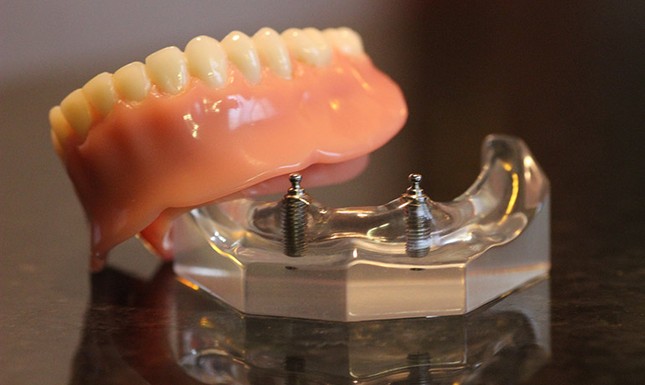

Пошаговое руководство по установке съёмного протеза на импланты